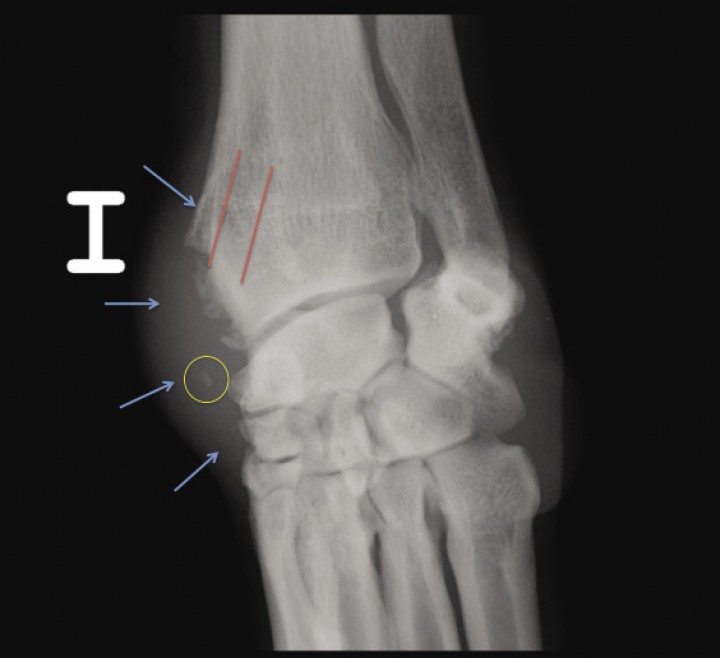

Analizando ambas proyecciones radiográficas podemos apreciar un marcado engrosamiento de los tejidos blandos asociados a la cara dorsomedial de la epífisis distal del radio y del carpo izquierdos (Fig. 2). Asimismo, se observa neoformación ósea irregular bien definida, subyacente al engrosamiento de tejidos blandos, desde la cara dorsomedial de la epífisis distal del radio distal (asociada al surco del tendón abductor del primer dedo) así como en el recorrido y la inserción del citado tendón en la parte medial del carpo (en la porción proximomedial del primer metacarpiano). En los tejidos blandos asociados al recorrido del tendón podemos apreciar una pequeña opacidad hueso homogénea con forma ovalada y bordes redondeados a nivel de la fila proximal del carpo.

<p>Mismas radiografías que en la Figura 1A. En la proyección AP se observa la localización del surco radial (líneas rojas), el engrosamiento de tejido blando medial (flechas azules) y la opacidad hueso en el transcurso del tendón abductor <em>pollicis longus</em> (círculo amarillo).</p>

Mismas radiografías que en la Figura 1A. En la proyección AP se observa la localización del surco radial (líneas rojas), el engrosamiento de tejido blando medial (flechas azules) y la opacidad hueso en el transcurso del tendón abductor pollicis longus (círculo amarillo).